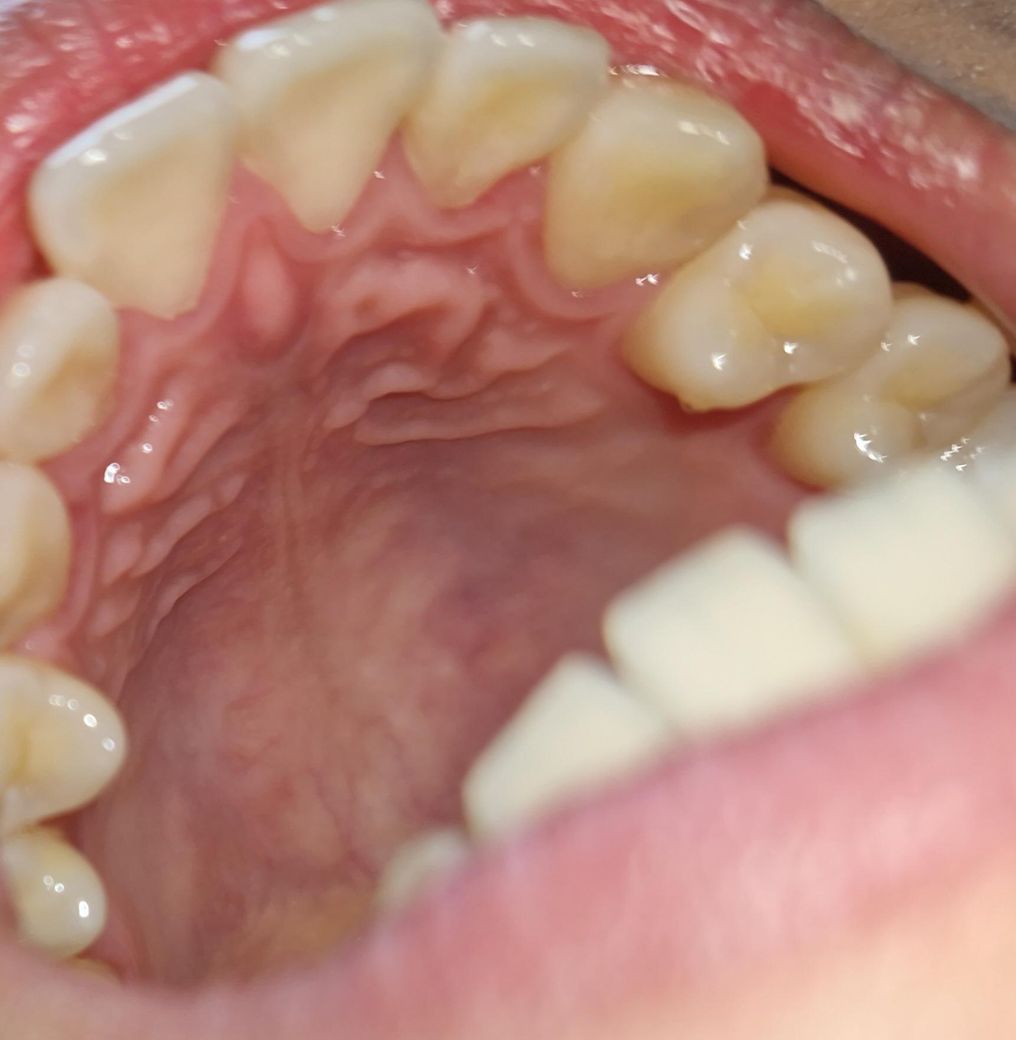

보통 바깥쪽 잇몸이 내려가고 사진으로 안쪽 잇몸이

내려가보이지는 않습니다. 중간중간 플라그와 염증소견이 약간씩 관찰되어 스케일링 한번 받으시면 좋겠습니다.

피가 나는 것은 염증이 있어서 그럴 가능성이 높으며 잇몸이 퇴축되어있다고 보이지는 않습니다.

잇몸퇴축이 심하진 않습니다 다만 치간 유두 부위가 부어있고 이는 위생관리 부족으로 생긴 염증같습니다 치과가서 스케일링 받아보세요